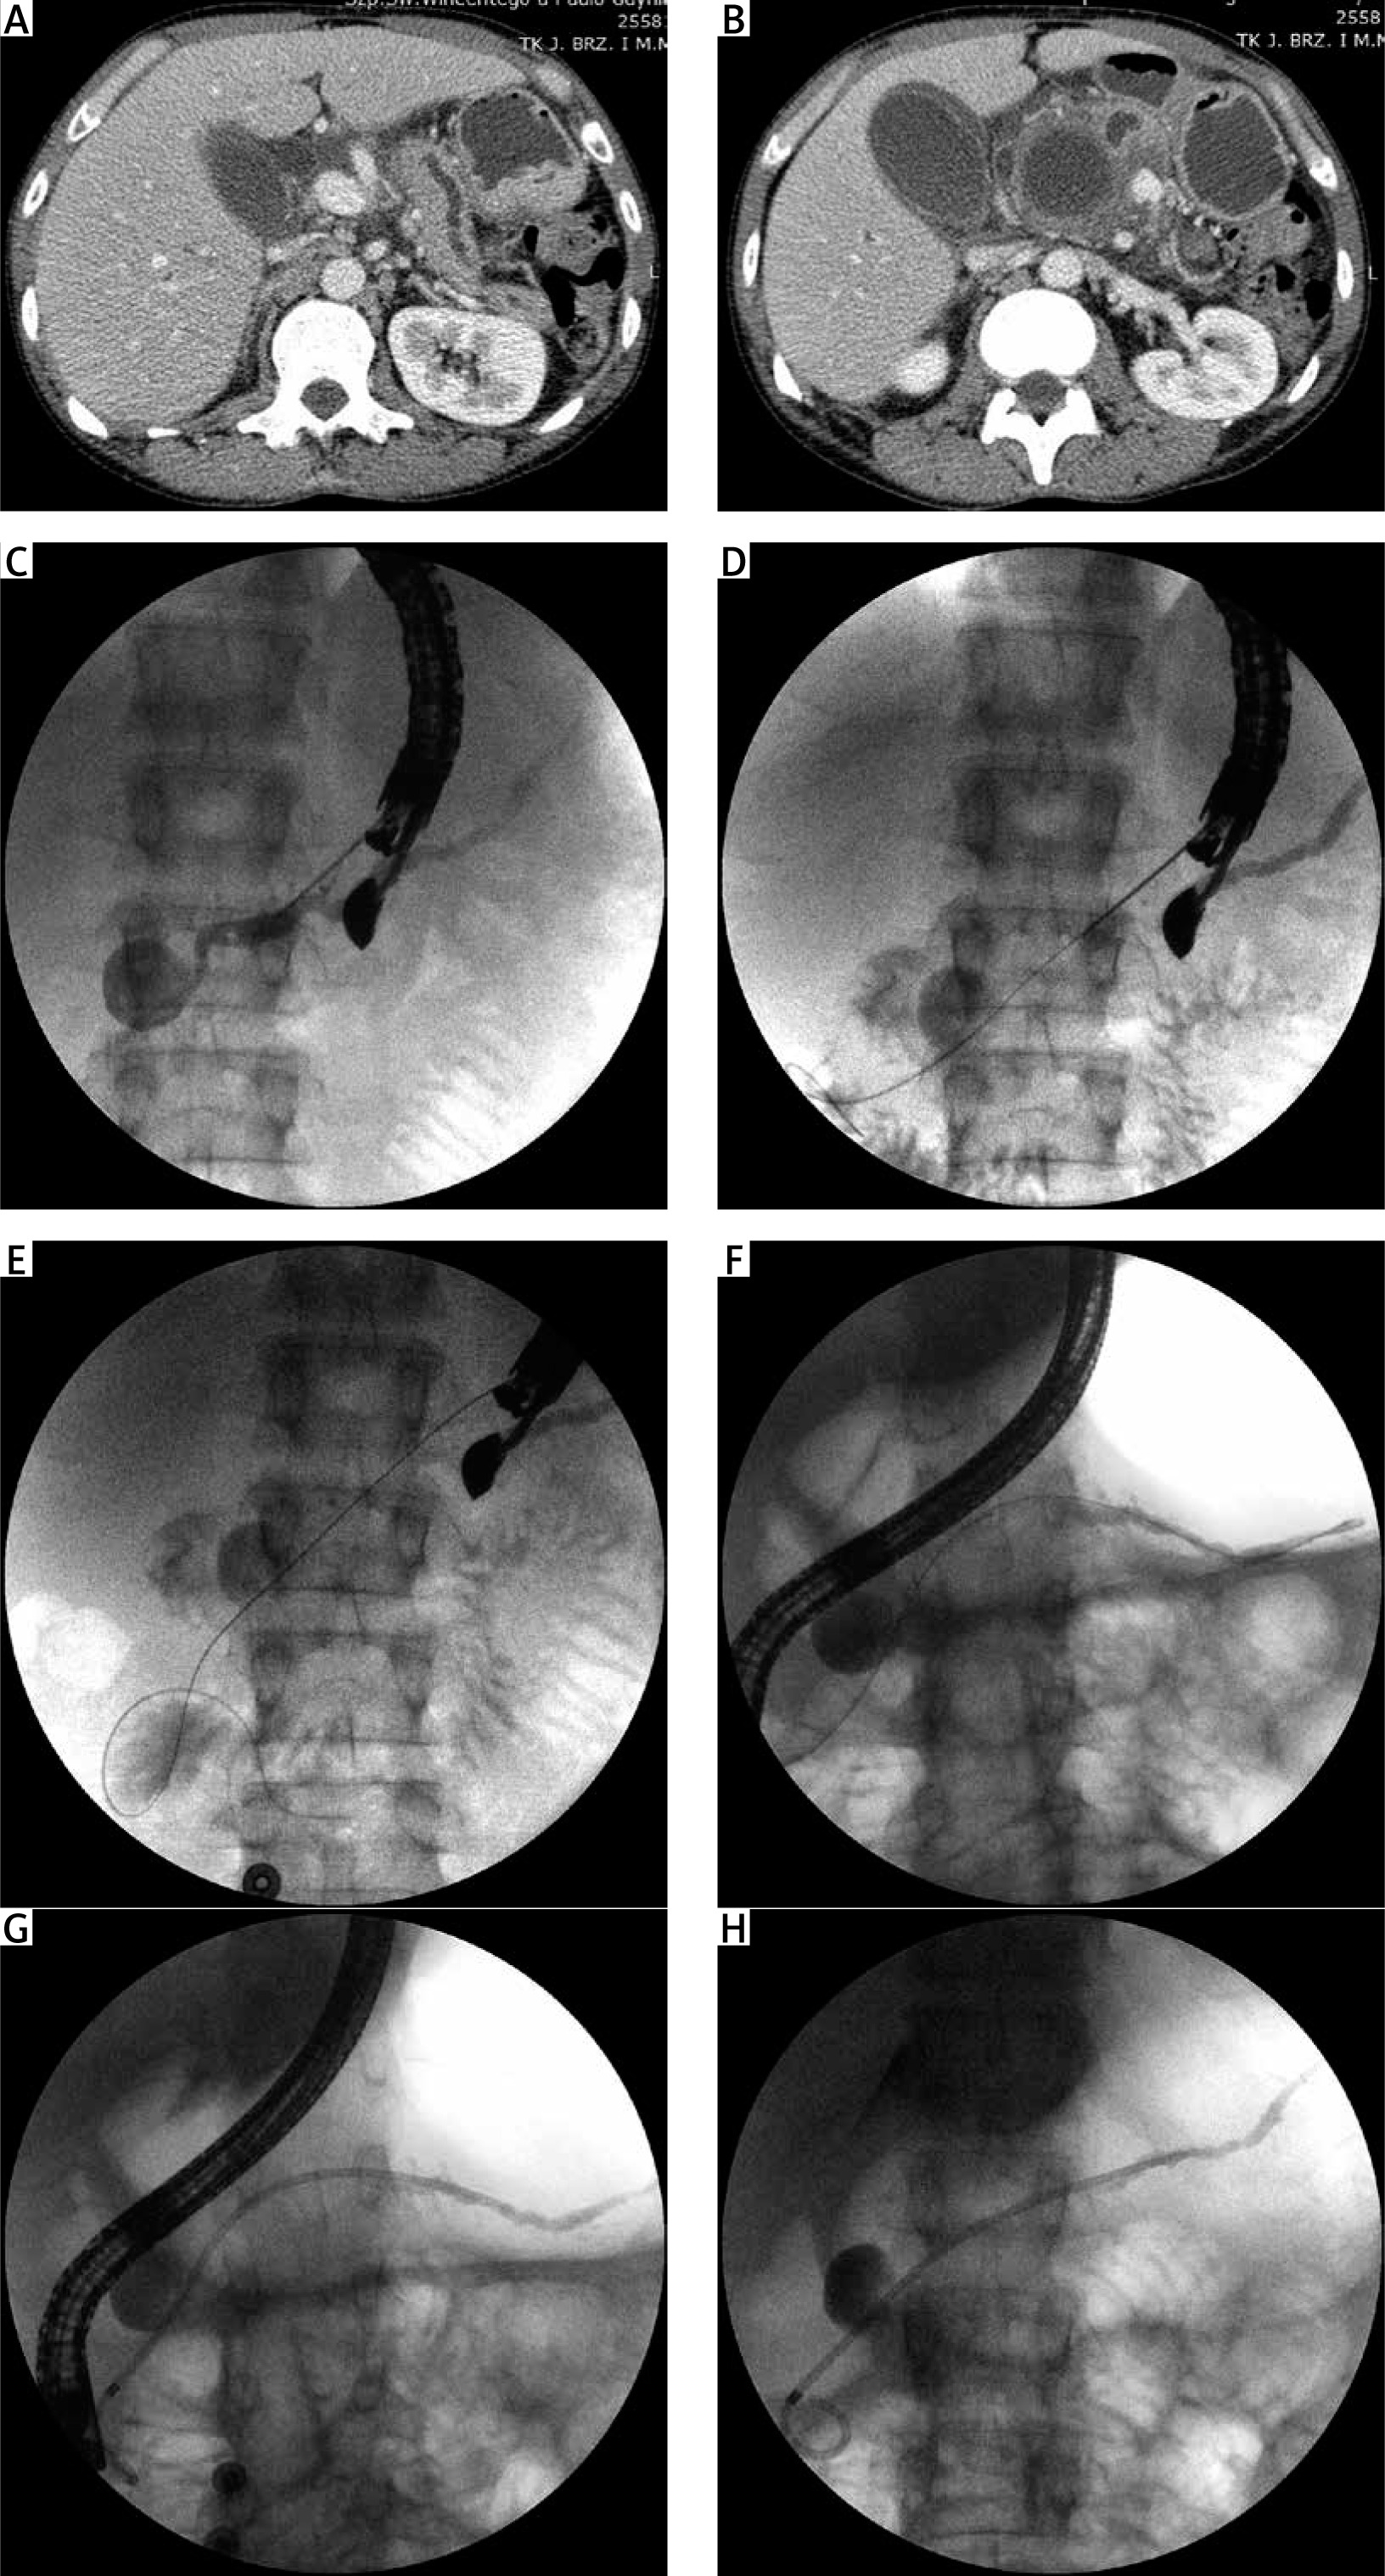

A 42-year-old male patient with chronic pancreatitis secondary to alcohol consumption was admitted to our department with complaints of severe abdominal pain and weight loss of about 25 kg within the last 2 months. Abdominal contrast-enhanced computed tomography was performed, revealing a pseudocyst (43 × 45 mm) in the pancreatic head (Figures 1 A, B), which caused duodenal stenosis and communicated with the dilated main pancreatic duct (MPD). The patient was qualified for endoscopic treatment; however, endoscopic ultrasound (EUS) imaging revealed that the pancreatic pseudocyst was surrounded by extensive inflammatory infiltration involving the duodenal wall. EUS-guided transmural drainage of the pseudocyst was not suitable because the distance between the lumen of the gastrointestinal tract and the lumen of the pseudocyst exceeded 30 mm, as shown in EUS imaging. During the endoscopic examination, inflammatory infiltration of the duodenal wall that narrowed the lumen of the gastrointestinal tract lumen was detected. It was also impossible to introduce the endoscope into the descending duodenum in order to localize the major duodenal papilla during endoscopic retrograde cholangiopancreatography (ERCP) for subsequent endoscopic transpapillary drainage of the pancreatic pseudocyst. Therefore, we decided to perform the EUS-guided rendezvous manoeuvre. A 19G needle was used to perform an EUS-guided puncture of the dilated MPD across the posterior wall of the gastric antrum. Contrast was administered via the needle, and this filled the MPD along its entire length (antegrade pancreatography), revealing partial disruption of the MPD within the pancreatic head, which resulted to leakage of contrast agent into the lumen of the pancreatic pseudocyst (Figure 1 C). The needle was used for transmural/transgastric introduction of a guidewire into the MPD, and the distal tip of the guidewire was placed within the duodenal bulb after passing it through the major duodenal papilla (Figures 1 D, E). The echoendoscope was then switched to a duodenoscope with the guidewire remaining in the transmural position within the lumen of the MPD and the duodenum. The duodenoscope was introduced into the duodenal bulb and the guidewire was grasped using endoscopic forceps. The MPD was catheterized selectively via the duodenal papilla (Figure 1 F). A 12-cm, 7-Fr pancreatic stent was then introduced along the guidewire, and its distal end was placed within the pancreatic tail so as to bridge the disruption’s site of the duct within the pancreatic head (Figures 1 G, H). The patient’s complaints were completely resolved during the postoperative period, and he was discharged home in good general condition with a recommendation to present for elective hospitalization in order to continue pancreatic endotherapy after 3 months.

Figure 1

Abdominal contrast-enhanced computed tomography scans (A, B) showing a pancreatic pseudocyst communicating with the dilated MPD. Fluoroscopic images showing the subsequent steps of EUS-guided rendezvous manoeuvre (C–H) at the MPD. C – Partial disruption of MPD and pancreatic pseudocyst are visible during antegrade pancreatography. D, E – A guidewire was introduced into the MPD, and the distal tip of the guidewire was placed within the duodenal bulb after passing it through the major duodenal papilla. F – The MPD was catheterized selectively through the major duodenal papilla. G, H – A 7-Fr pancreatic stent was introduced along the guidewire, and its distal end was placed within the pancreatic tail so as to bridge the disruption’s site of the MPD within the pancreatic head